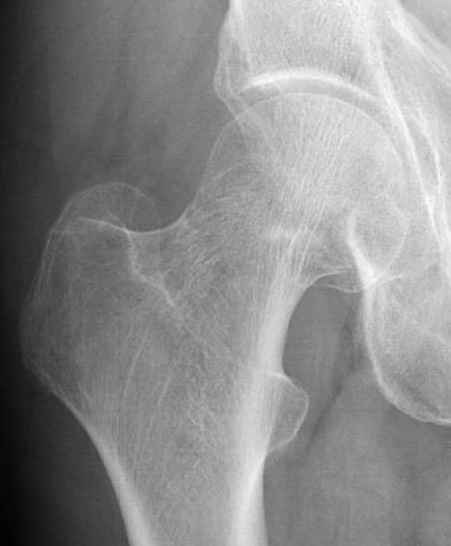

Уважаемые коллеги,

Хотели бы знать тактику лечения 62 летнего больного, отягощенного

алкоголизмом, с жалобами на боли в правом тазобедренном суставе.

Не смогли добиться вразумительного ответа по поводу анамнеза травмы,

клинически движения ограничены из-за боли, сделанные снимки сустава

представлены. На КТ неполный перелом шейки. Начали профилактику

возможного Алкогольного Делирия.

Дальнейшее рекомендации, оставить как есть, или профилактическая

перкутанная фиксация?